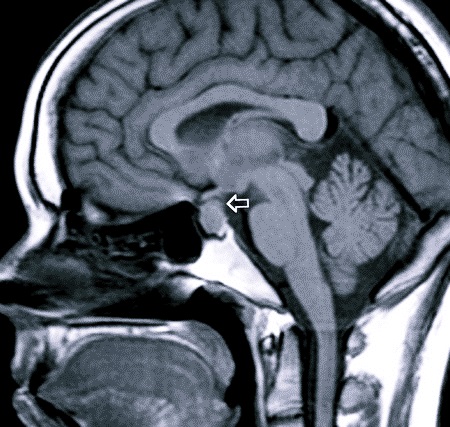

Гипофиз – это железа внутренней секреции, которая вырабатывает гормоны, регулирующие деятельность других желез и функций организма. Располагается гипофиз в турецком седле – углублении клиновидной кости черепа. Орган разделен на два отдела, вырабатывающих разные гормоны – аденогипофиз и нейрогипофиз.

| Рентгенография черепа | Расширение турецкого седла, атрофия его дна, утолщение лицевых костей. Рентгеновский снимок делают в двух проекциях. |

| КТ и МРТ | Визуализация самой опухоли — можно определить образование от 2 мм в диаметре. МРТ позволяет с большой точностью распознать инвазивный рост опухолевого образования. |